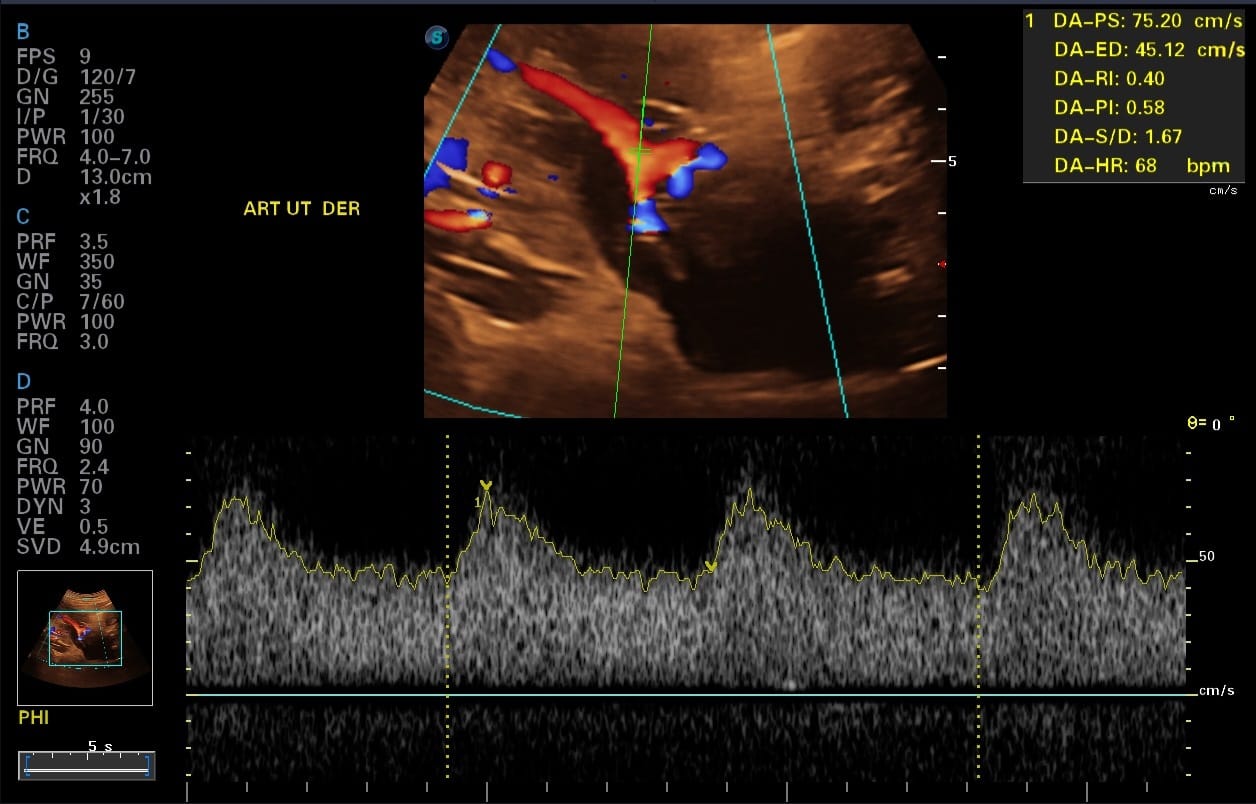

- Evaluacion materna, mediante la evaluacion de arterias uterinas que condicionen a la Preeclampsia (aumento de la Presion Arterial), Diabetes Gestacional, Parto Prematuro, e otros.

Objetivo 2: Evalua riesgo de Preeclampsia (Aumento de la Presion Arterial).

Evaluación de la posición de la placenta y el flujo sanguíneo hacia la placenta y el feto mediante ecografía Doppler color. (Doppler de Arterias Uterinas, Doppler de Arteria Cerebral Media, Doppler de Arteria Umbilical, Doppler de Ductus venoso, Doppler de Itsmo Aortico. e otros).